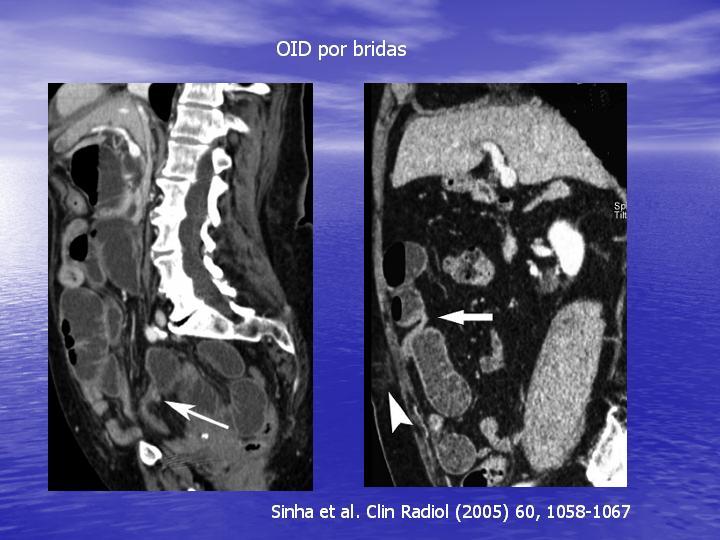

Obstrucción Intestinal: Estudio Diagnostico y Manejo inicial